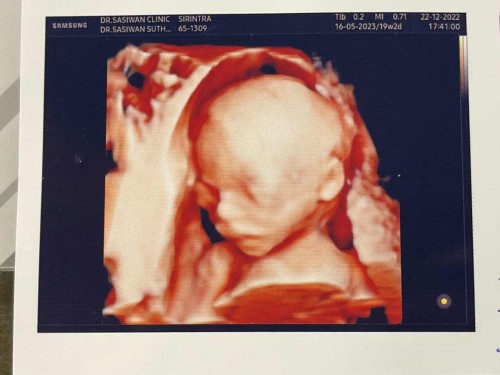

มีใคร อัลตราซาวด์ 4Dตอน 20 วีคแล้วบ้างคะ ตื่นเต้นมากเลยค่ะเริ่มเห็นหน้าลูกชัดๆบ้างแล้ว

อันนี้ซาวด์ตอน 17wจะ18wค่ะ เเม่บ้านนี้รอไปซาวด์อีกทีช่วงเกือบๆ6-7เดือนค่ะ จะได้เห็น น้องได้ชัดๆ ไปหลายรอบพ่อบ้านนี้บ่นค่ะ เพราะเเพง😆บอกให้เก็บเงิน ซื้อของให้ลูกดีกว่า

น้องน่ารักจังเลยค่ะ ทางนี้รอไปซาวด์ตอน28วีคค่ั หมอนัดซาวด์4Dตอนนั้น